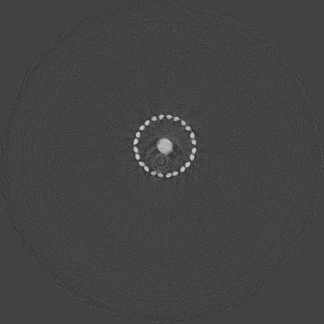

Figure 3 shows a single slice spectral reconstruction of the Ti phantom. The cupping effect is prominent in the low energy range and decreases in the high energy acquisitions. The thresholds were determined to provide a trade-off between reduced photon noise and cupping effect. The spectral images for the energy ranges 55 to 80 keV and 62 to 80 keV exhibit reduced cupping effect while the 15 to 80 keV reconstruction has low quantum noise and shows good contrast in non-metal regions. In figure 4, a horizontal line profile passing through the origin of the metal cylinder shows cupping effect in the different energy ranges. Without the use of any hardware filters, a significant reduction in the cupping effect is noticeable in figure 4c. The reconstruction corresponding to the energy range from 62 to 80 keV suffers from severe photon limitation giving rise to statistical noise. Any significant increase in tube current and/or exposure time for this scan resulted in detector saturation in non-metal regions.

Refer to caption

(a) 15 to 80 keV

(b) 35 to 80 keV

(c) 55 to 80 keV

(d) 62 to 80 keV

Figure 3: Spectral reconstruction of Ti cylindrical phantom. High energy ranges shows reduced cupping effect.